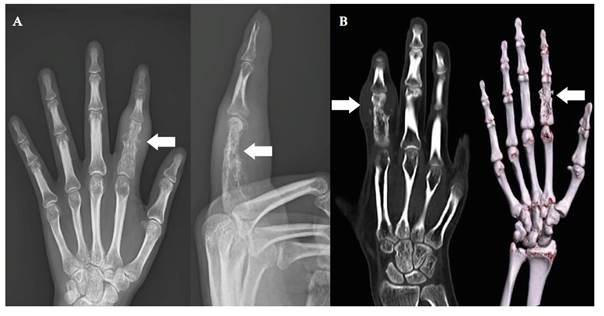

Los resultados de análisis realizados en el hospital de origen mostraron: leucocitos 12 200 /µl, hemoglobina de 12,4 gr/dl, eosinófilos 2%, linfocitos 9%, proteína C reactiva en 11,7 mg/dl, velocidad de sedimentación globular de 12 mm/hora. La prueba rápida de VIH fue no reactiva. Al ingreso se realizó una ecografía de partes blandas del segundo dedo de la mano derecha, que mostró una colección periósea comprometiendo la falange proximal media, y signos de lisis ósea de la falange proximal. La radiografía de la mano derecha evidenció un aumento de partes blandas, alteración de la morfología de la falange proximal del segundo dedo de la mano derecha con signos de osteólisis (figura 1A). La tomografía computarizada de la mano derecha sin contraste reveló un incremento en el espesor de partes blandas que condiciona cambios osteolíticos a nivel de la falange proximal del segundo dedo (figura 1B).

Figura 1 Radiografía en vista frontal-lateral (A) y Tomografía computarizada de mano derecha (B): muestran lesión expansiva que compromete falange proximal, articulación interfalángica y base de falange media de segundo dedo, asociados a cambios osteolíticos.